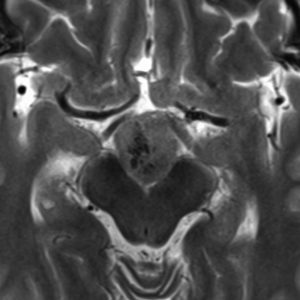

1968年 18歳の時に頭痛嘔吐で発症しました。第3脳室腫瘍と閉塞性水頭症の診断だけで,シャント手術を受けました。手術も化学療法も放射線治療もされていません。下の画像は60代で撮影されたものです。この例では,第3脳室内に増大した大きな毛様細胞性星細胞腫が,視床下部下垂体障害を出すことなく,自然経過で増大停止 growth arrest して,カチカチに固まってしまうということを教えてくれます。でも,こんなに都合よく経過観察できる例も珍しいです。

CTでは強い石灰化があります。右のT2強調画像では腫瘍は等信号,視交叉の後ろにあります。内部の低信号は石灰化です。